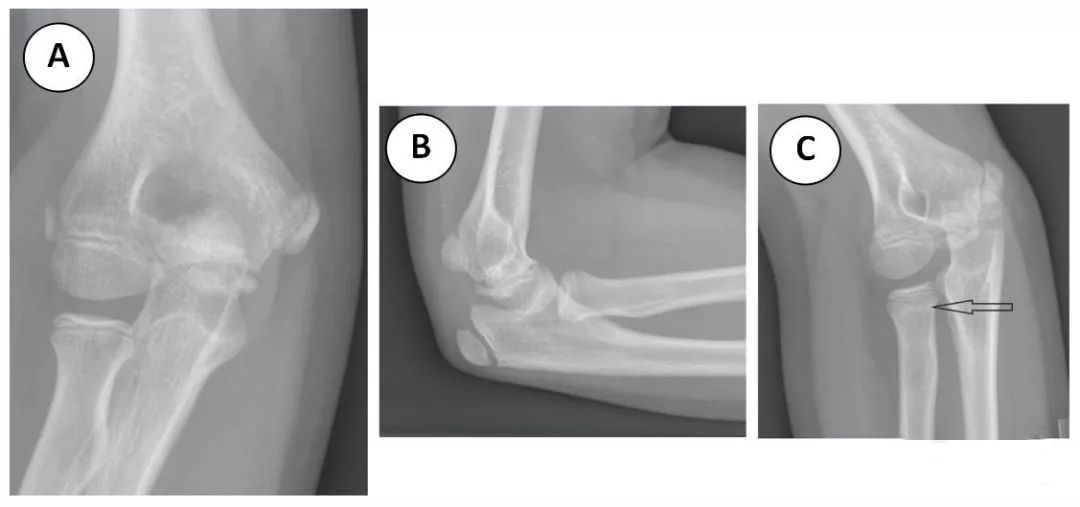

图 9 (A) 肘部正位片未显示任何异常,特别是桡骨颈。(B) 肘关节侧位片未见关节积液。(C) 肘部前视图显示桡骨颈硬化 (箭头),提示 Ⅱ 期愈合的无移位桡骨颈骨折。